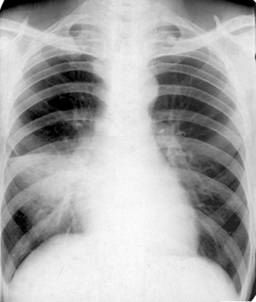

照片名称:风心病,梨型心